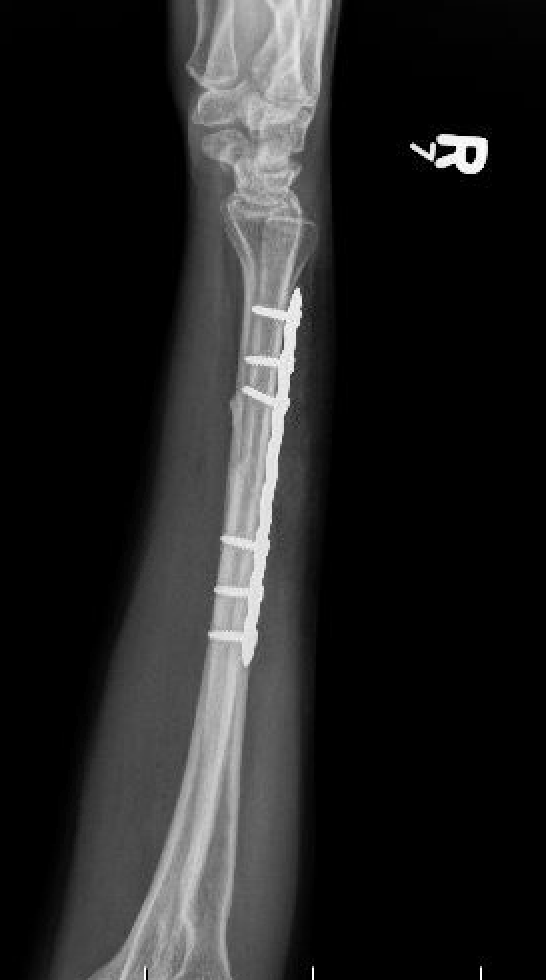

Options

Compression plating

Results

- IM K wire v plate in 54 patients

- 3 nonunions with plate, none with IM wire

- 70% of patients required wire removal

- 11% of patients required plate removal